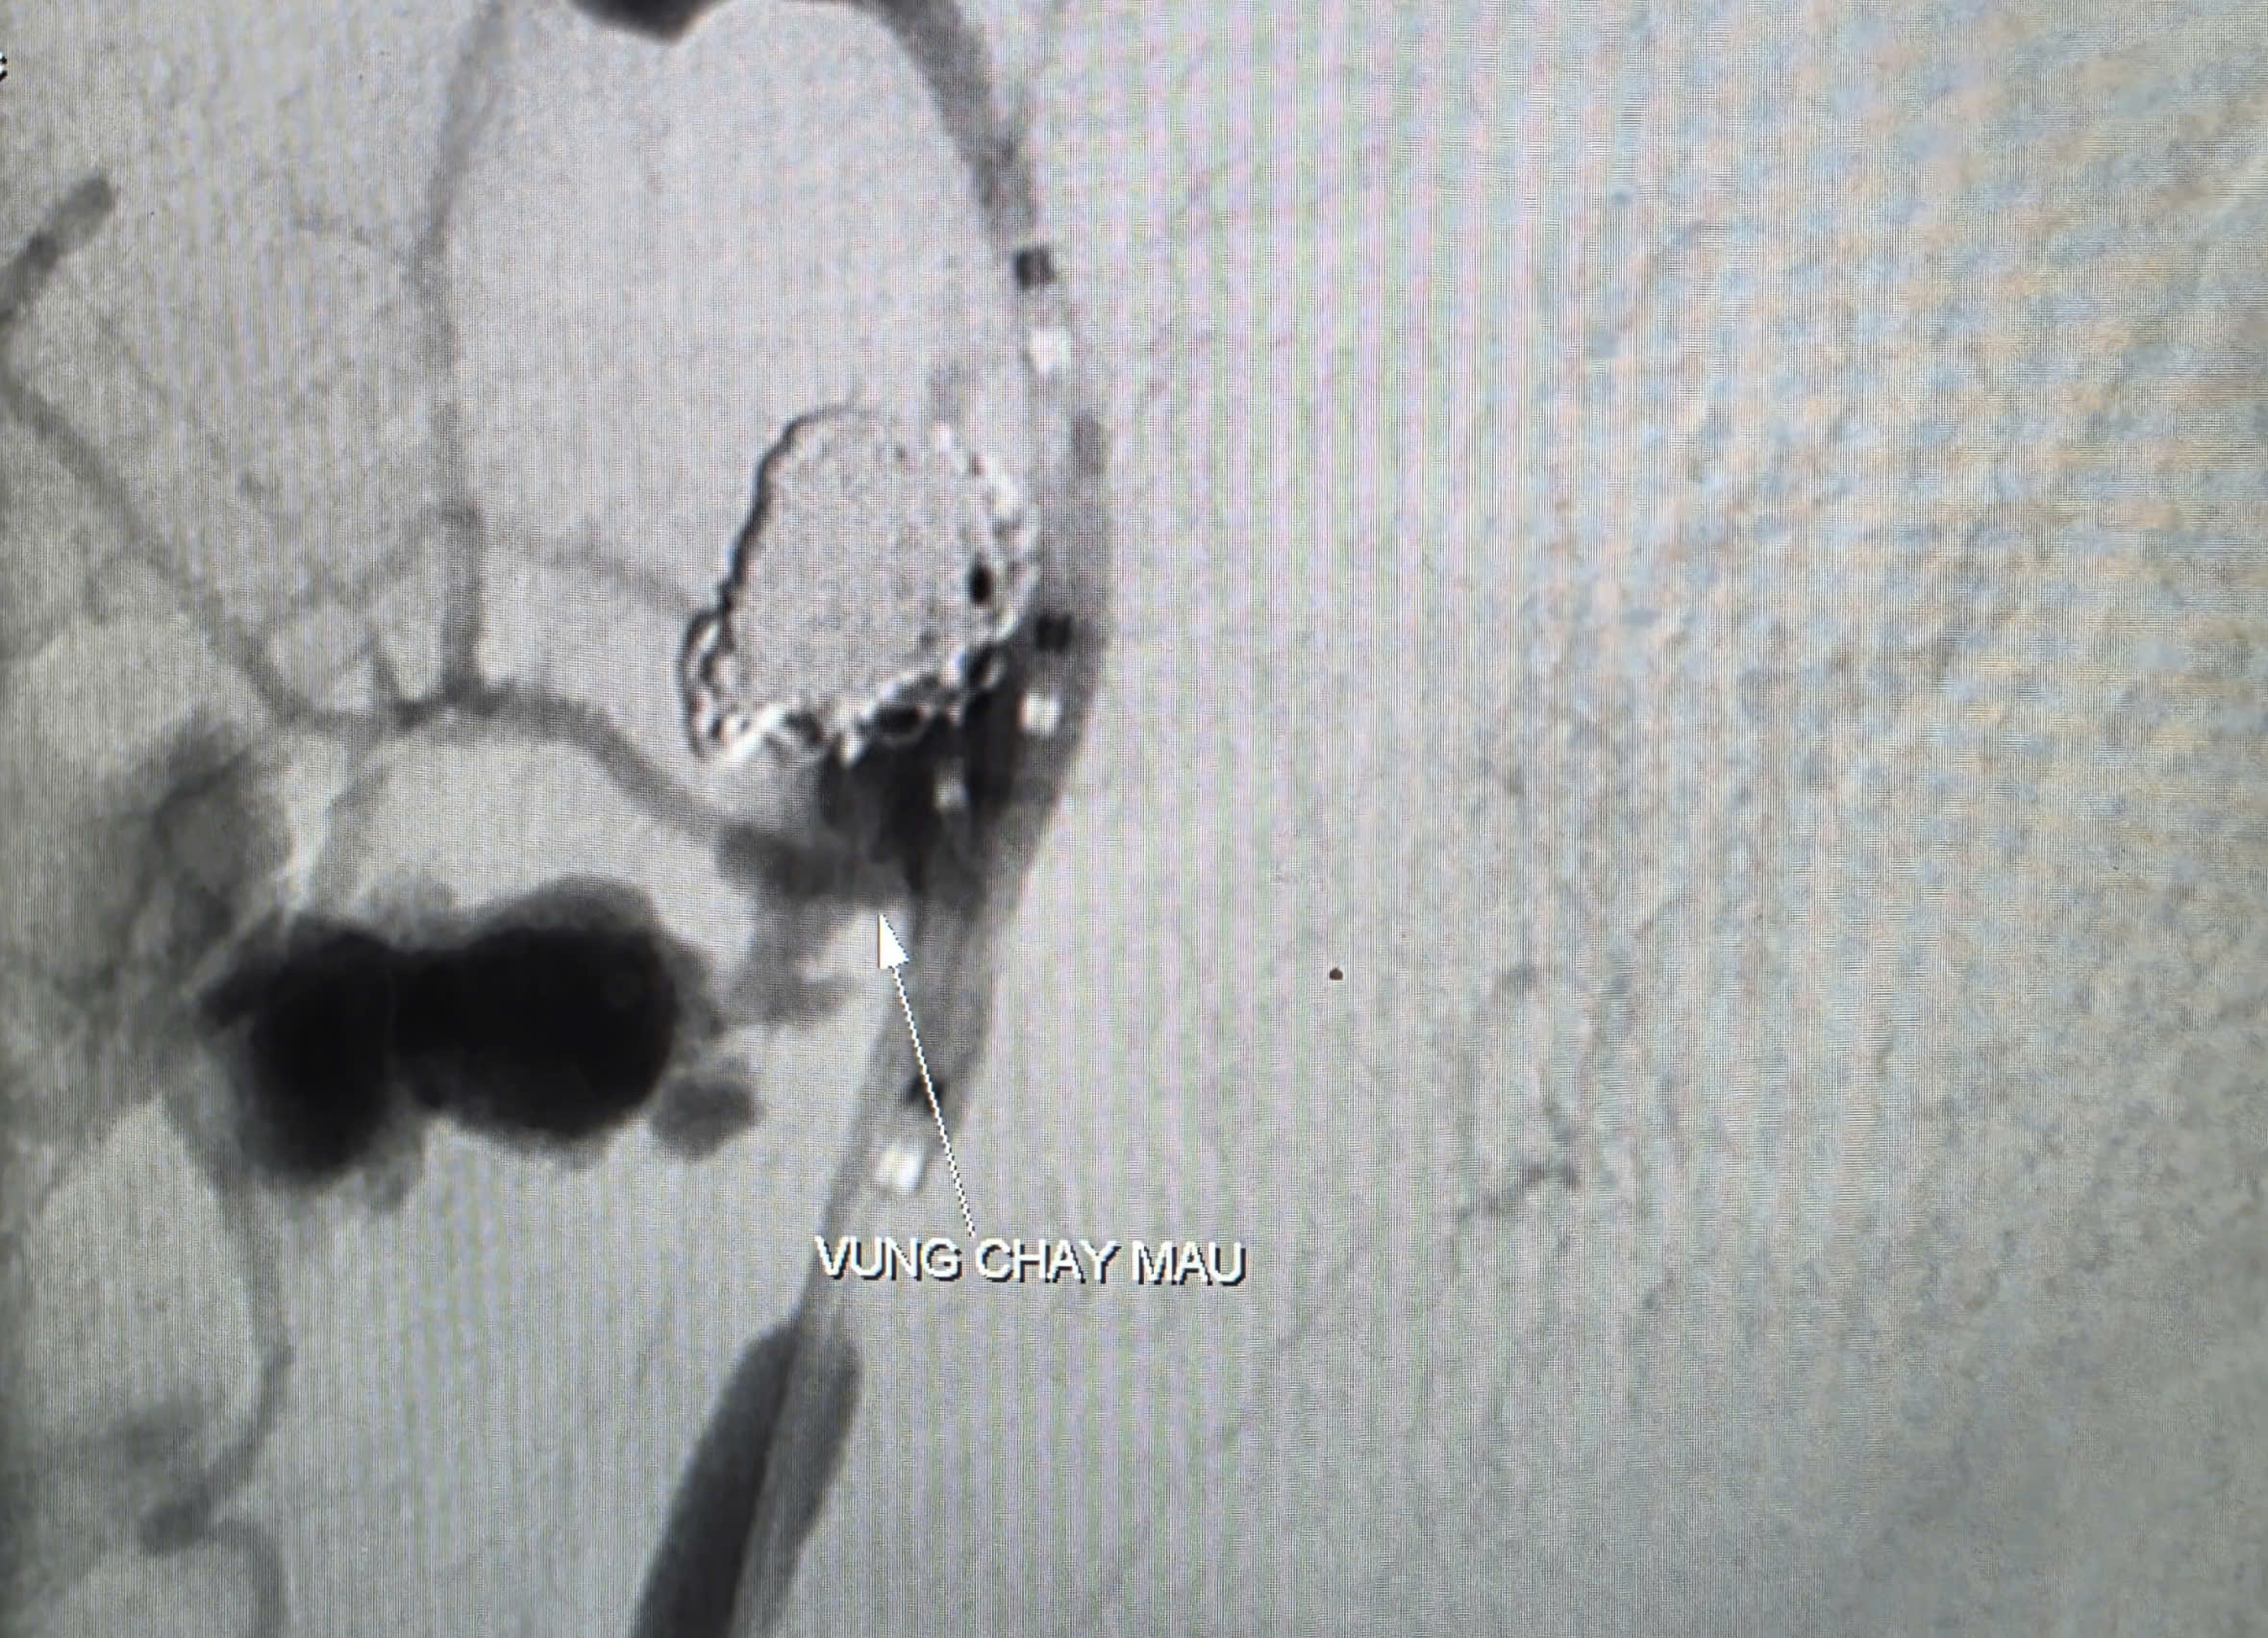

Hình ảnh chụp CT Scan ghi nhận bệnh nhân có ổ giả phình động mạch cảnh trong phải đoạn cổ, dưới nền sọ, cổ túi phình rộng và đang chảy máu

Kết quả CT Scan ghi nhận tổn thương vùng dạng khối choán chỗ khoang niêm mạc hầu lệch phải, xâm lấn vào động mạch cảnh trong tương ứng, có dấu hiệu thoát thuốc cản quang vào vùng hầu - họng cạnh bên và ổ giả phình động mạch cảnh trong đoạn dưới nền sọ.

Trước nguy cơ bệnh nhân mất máu ồ ạt, các bác sĩ quyết định thực hiện chụp và can thiệp cầm máu dưới mạch số hóa xóa nền (DSA). Kết quả ghi nhận ổ giả phình động mạch cảnh trong phải đoạn cổ, dưới nền sọ, kích thước 4,2 x 4,8 mm, cổ túi phình rộng và đang chảy máu.